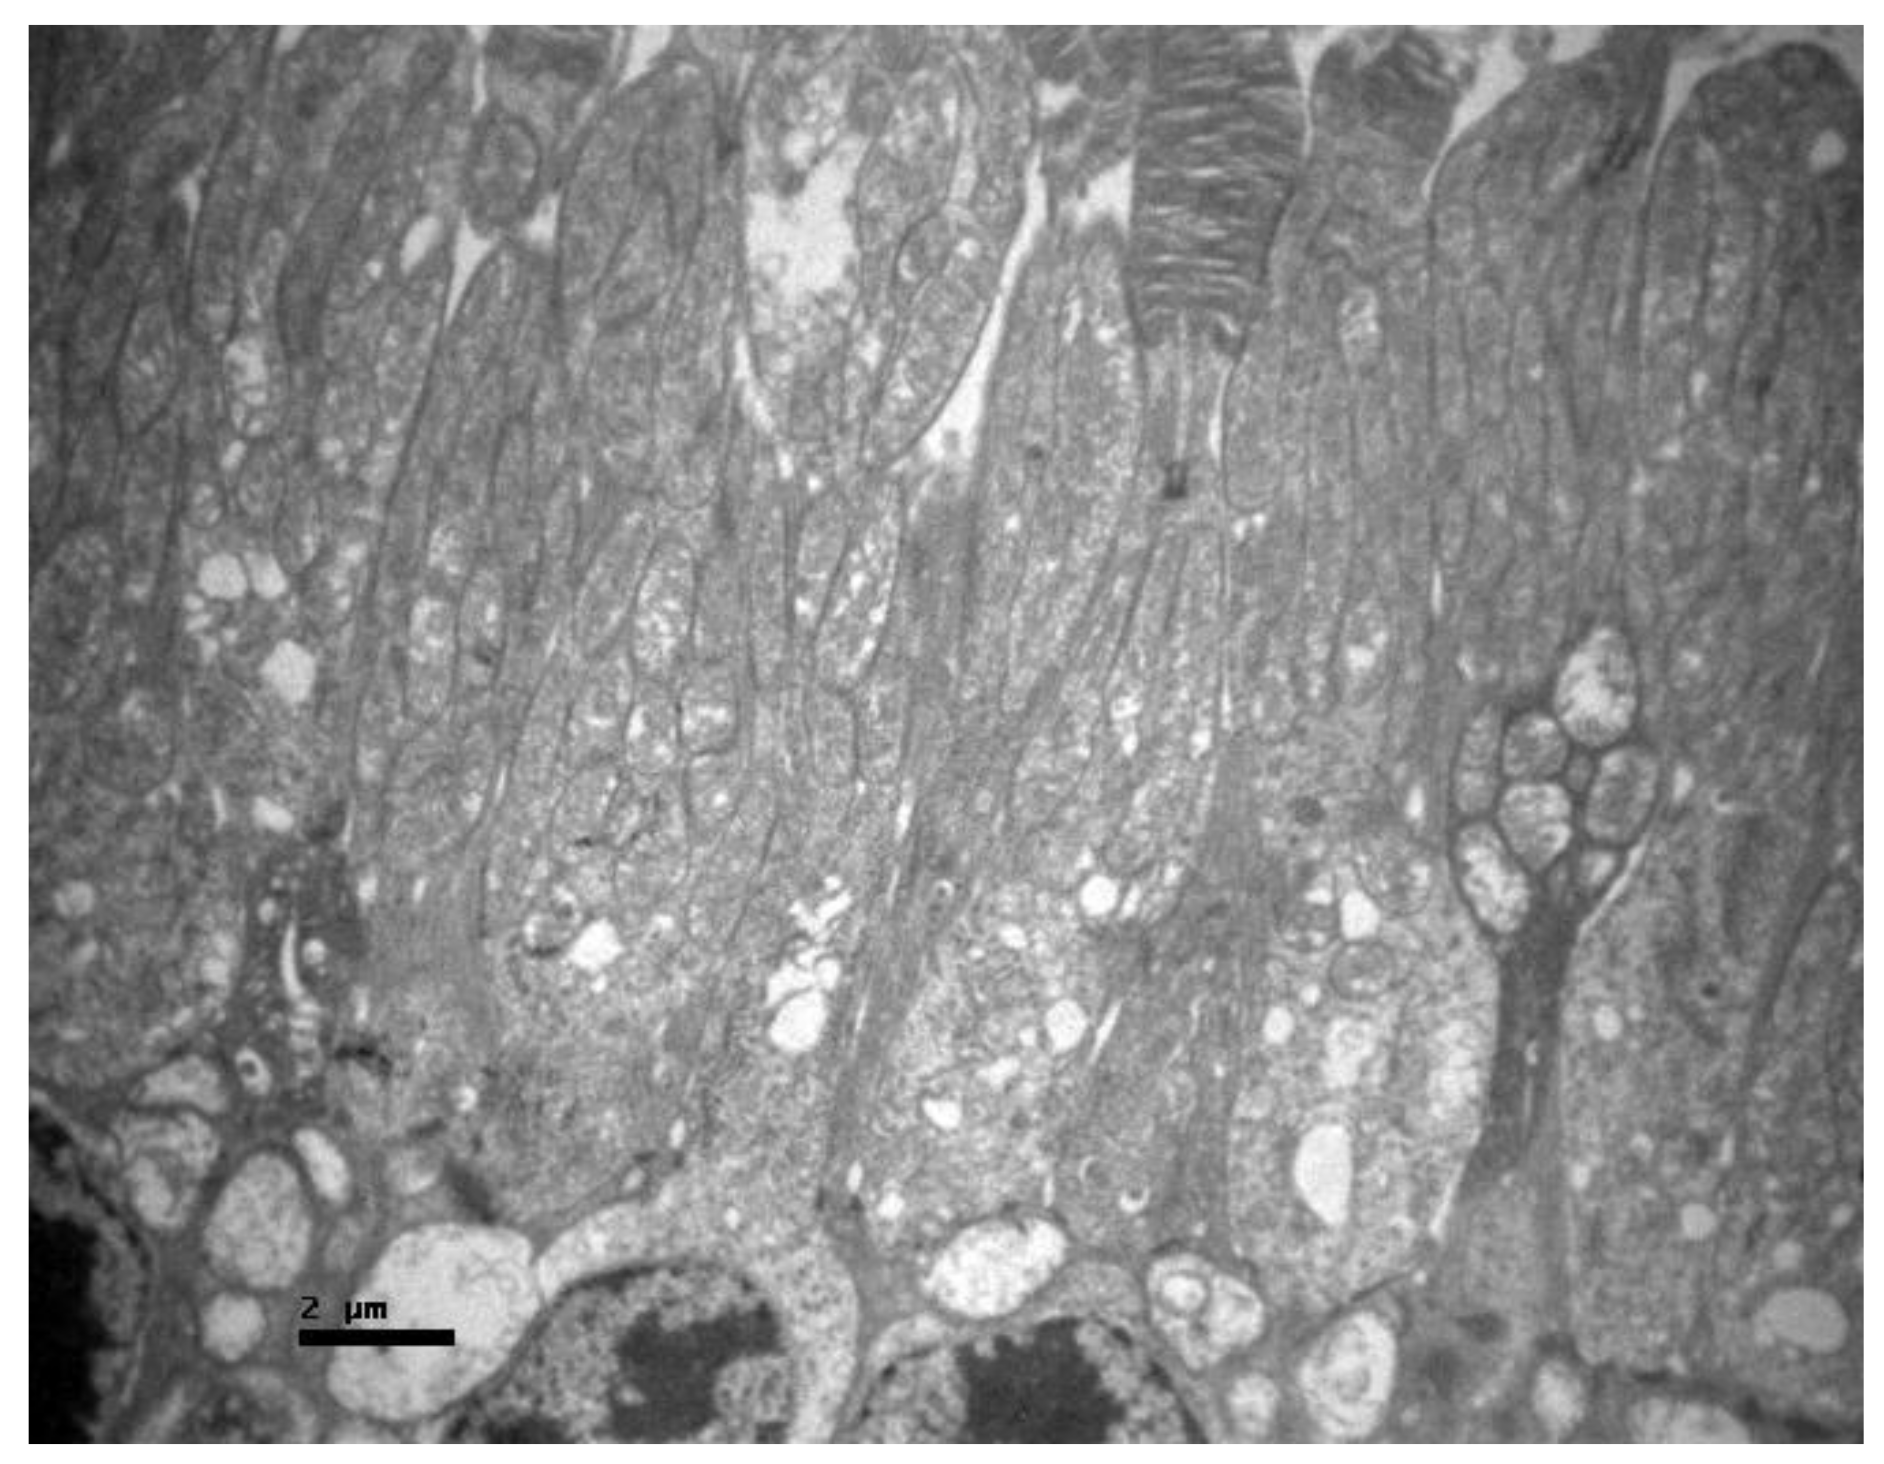

2.1. Group C